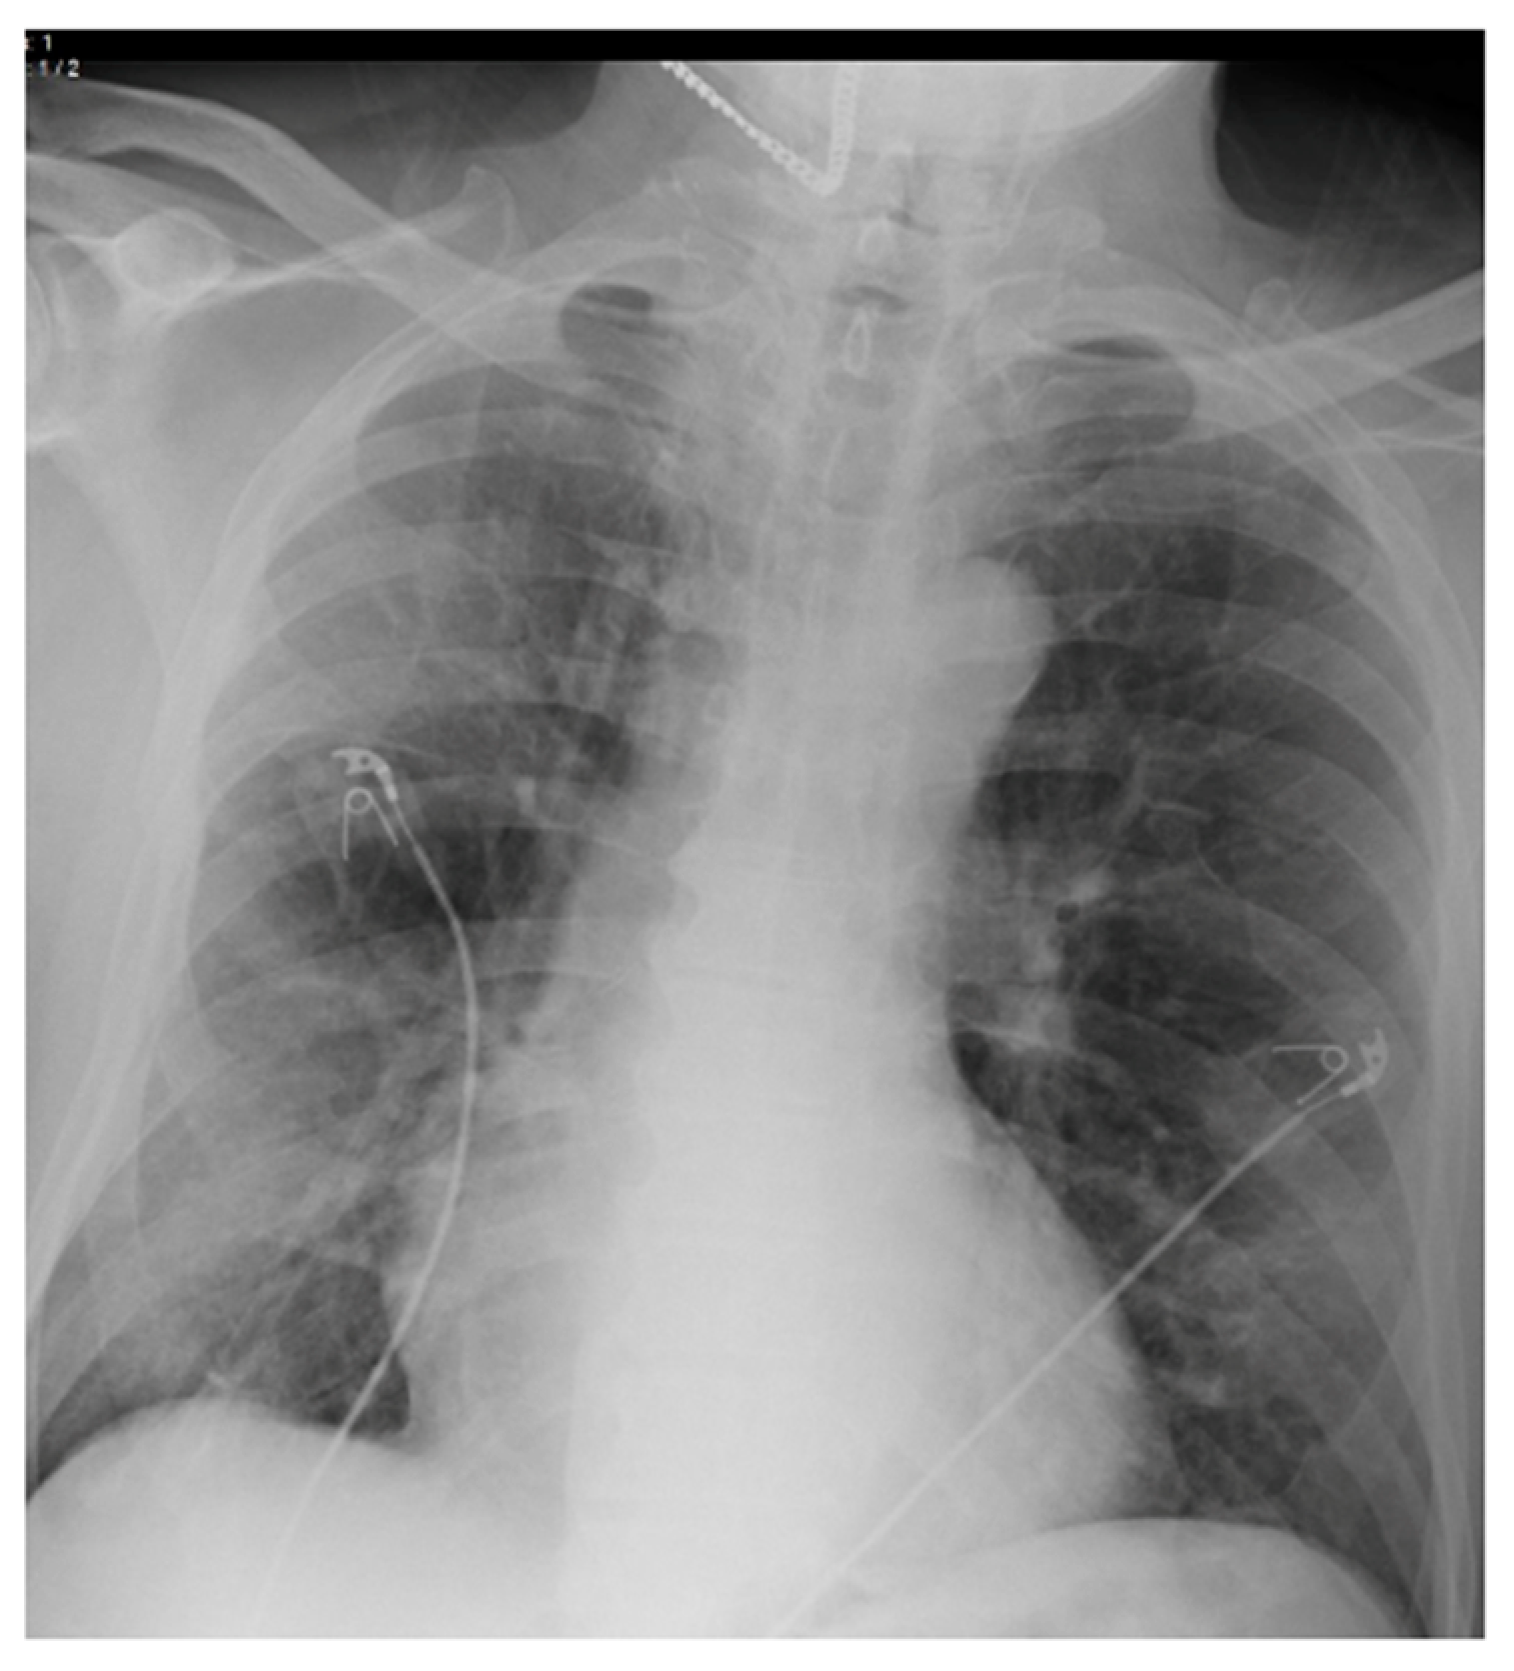

2.3. Imaging and Analysis

| CXR Severity Score ** | 3.0 (1.0, 4.0) | 3.0 (0.0, 3.0) | 3.0 (3.0, 6.0) | |

| Radiology Findings | |

| No | 149 (23.7%) |

| Yes | 479 (76.3%) |

| Radiologic Characteristics | |

| Distribution | |

| Unilateral Unilobar | 64 (13.4%) |

| Unilateral Multilobar | 21 (4.4%) |

| Bilateral—not diffuse | 63 (13.2%) |

| Diffuse Bilateral | 331 (69.1%) |

| Opacity | |

| Hazy or Interstitial Opacities | 357 (74.5%) |

| Dense Opacities | 122 (25.5%) |

| Specific Patterns | |

| Diffuse-Bilateral with hazy opacities | 256 (53.4%) |

| Diffuse-Bilateral with dense opacities | 75 (15.7%) |

| Unilateral-Unilobar with Hazy opacities | 49 (10.2%) |

| Bilateral with predominance with hazy opacities | 37 (7.7%) |

| Bilateral with predominance with dense opacities | 26 (5.4%) |

| Unilateral-Multilobar with Hazy opacities | 15 (3.1%) |

| Unilateral-Unilobar with dense opacities | 15 (3.1%) |

| Unilateral-Multilobar with dense opacities | 6 (1.3%) |

| CXR Severity Score | 1.184 (1.054, 1.330) | 0.005 |

| CXR Severity Score | 0.132 | 0.046 | 1.141 (1.003, 1.299) |